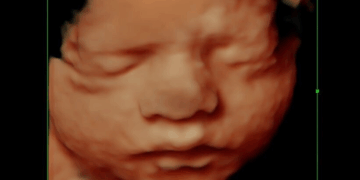

On April 28, 1983, an eight-year-old boy playing by his yard near Little Rock’s Cantrell Road discovered baby Mary Rose Doe lying dead in a drainage ditch. Mary was 16 inches long and weighed five pounds. She was seven months gestation, with a…